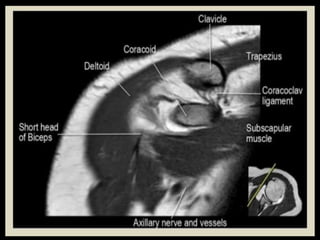

• 120.